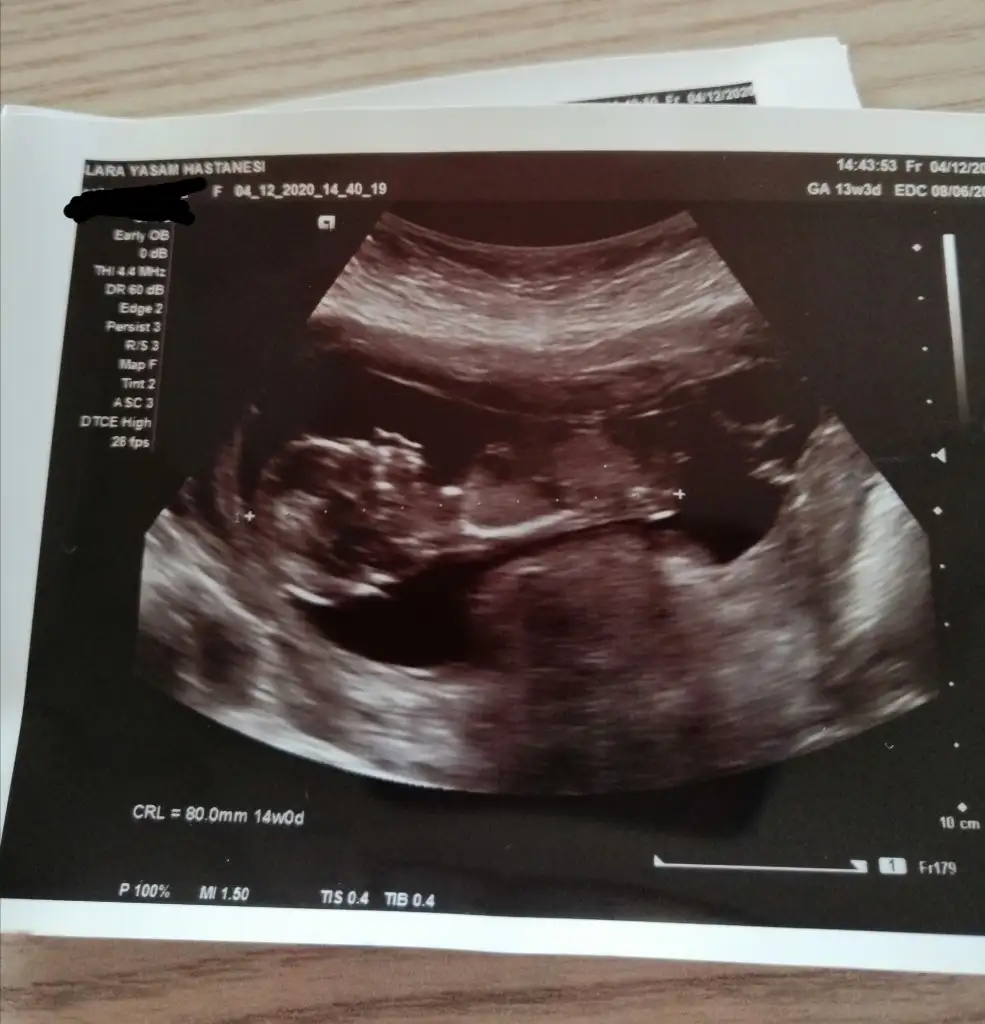

dr soylemeden siz gorun genital nub teorisi ( bebegin cinsiyeti)

5 kasimda gitmistim bi oncekinde 10 haftalik